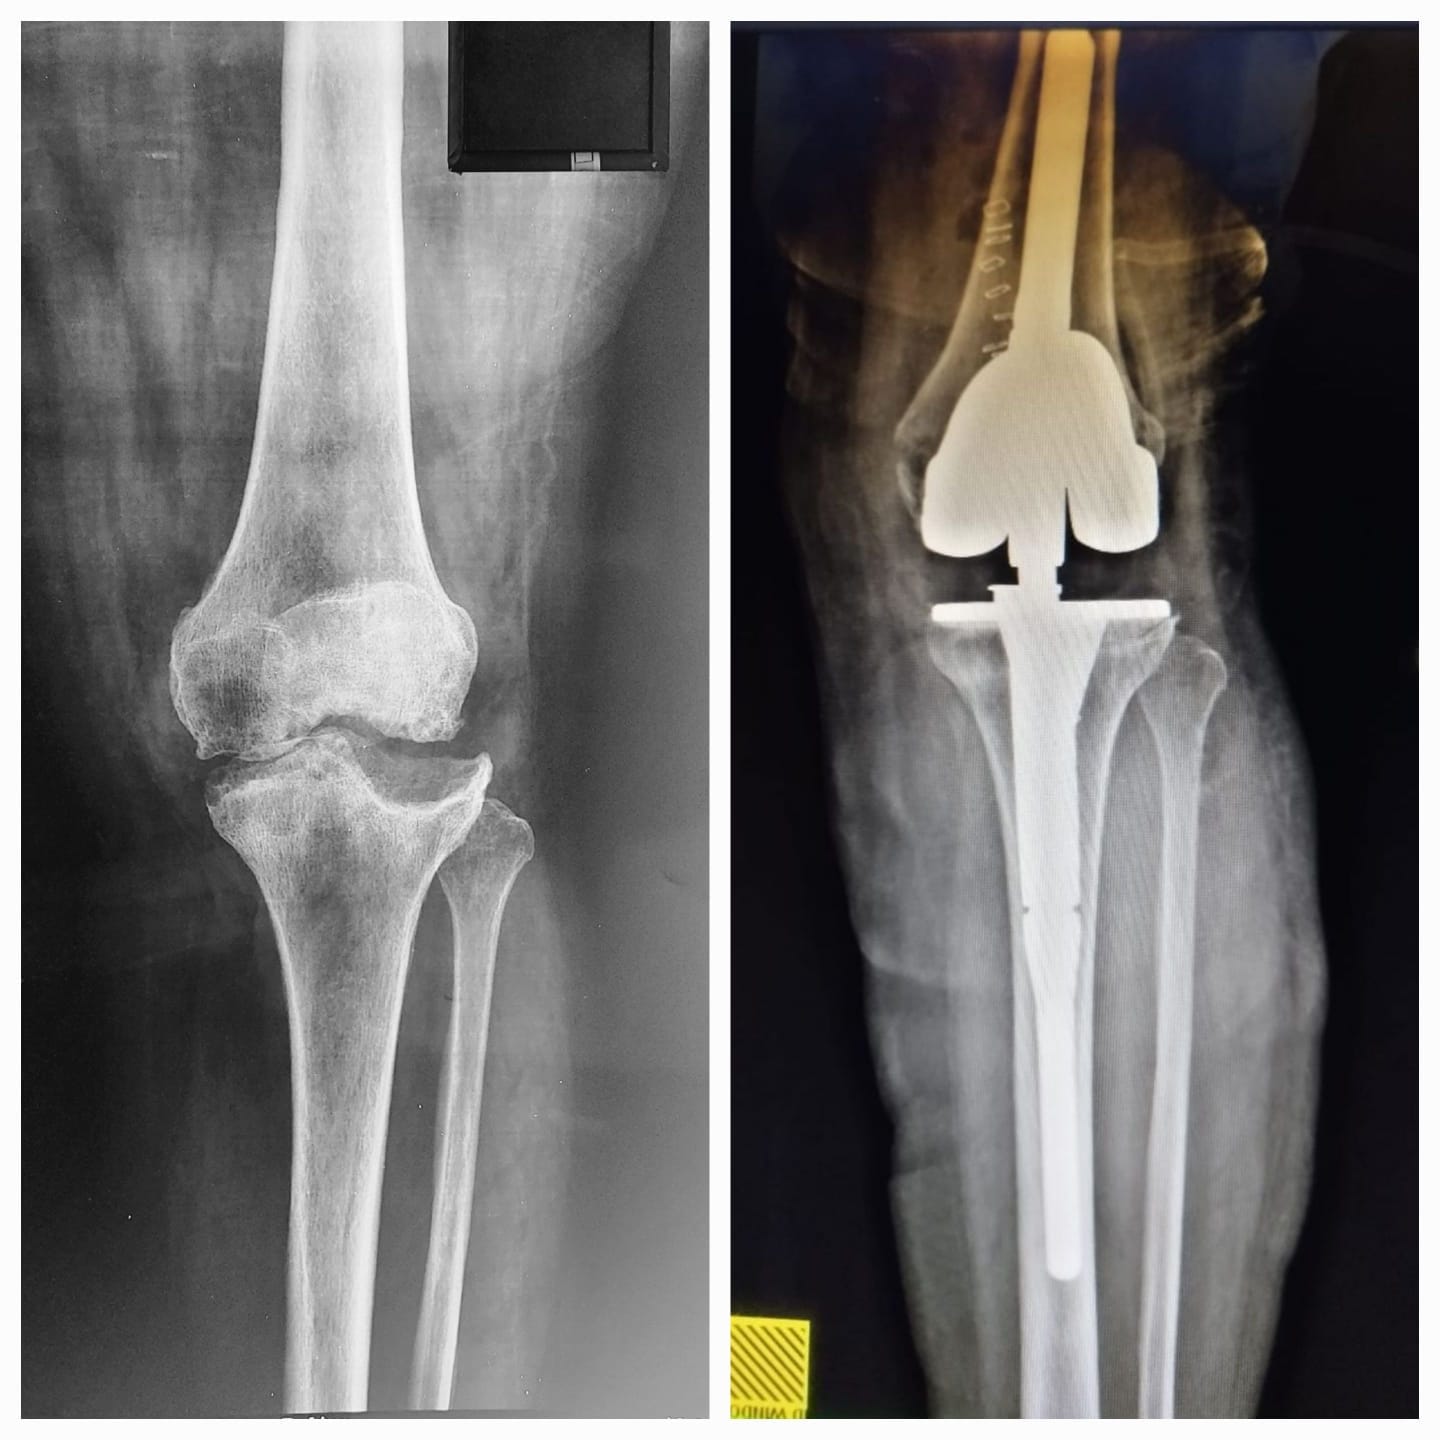

فريق طبي جراحي في مستشفى ابن سينا يجري عملية نوعية معقدة لمريضة تعاني من سوفان شديد في الركبه .

اجرى فريق طبي جراحي في مركز ابن سينا التخصصي لجراحة العظام والكسور و تبديل المفاصل عملية تبديل مفصل...

فريق طبي جراحي في مستشفى ابن سينا يجري عملية نوعية لمريضة تعاني من سوفان شديد في الركبه .